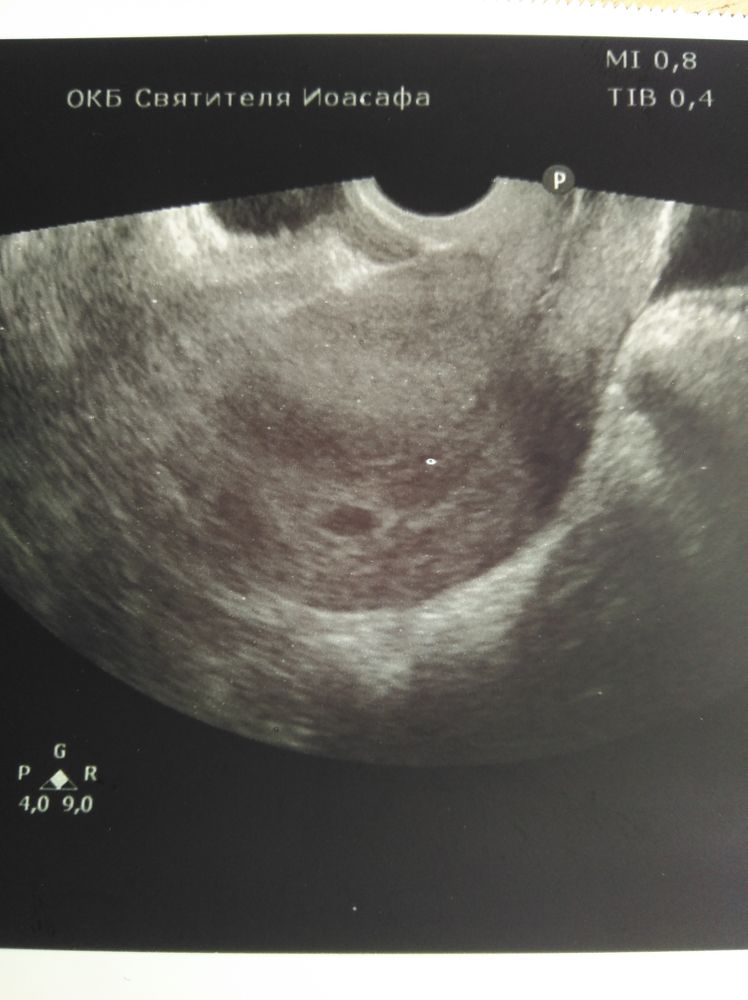

21 дпп побывала баба на узи. Моя ре свалила в отпуск, я конечно в печали, что рыба моя меня покинула, делала узи мне не особо опытная ре. За 2 секунды узи выяснилось, что есть ПЯ 10 мм одно, может 2, но это не точно, но точно есть 1😂😂😂 ЖМ не разглядывали, и вообще все рано, приходите через 2 недели, разберемся... Ну и погадаем на узи, кто сколько видит (узи отвратного качества)

Kate Agaeva, вот теперь понять бы что это за черная хера блуда в матке, рядом с эмбрионом

Kate Agaeva, так сколько ты видишь штук? я вроде 1, а если присмотреться 2...но он какой-то большой, чтож лошадь в 10 мм ре не разглядела?

Шепокляк_, я вижу реально одно то что можно принять за ПЯ

для дилетантов типа меня еще бы матку обвести.

Вижу два 🤷🏻♀️ растите здоровенькими самое главное

Если прям по стрелкам смотреть, то вроде два. Ждём второе УЗИ разгадку🤞

Я вижу два и вижу даже желточные мешочки😁